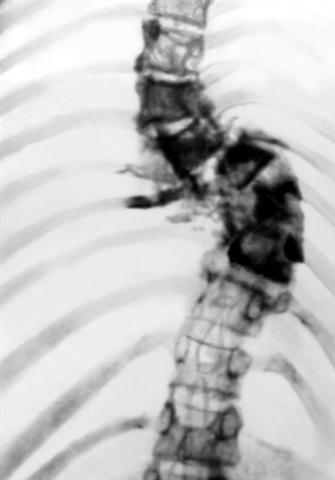

Рис. 1. Рентгенограмма позвоночника (прямая проекция) при сколиозе, обусловленном нейрофиброматозом: резкое боковое искривление в грудном отделе позвоночника.